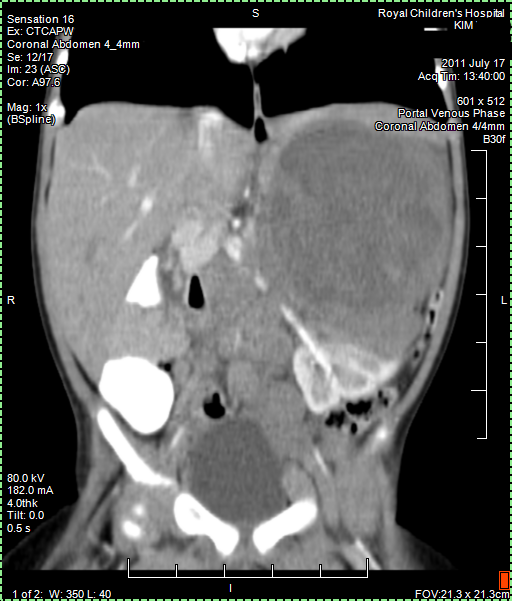

30 September 2011, Friday

Today we got the Radiology Report back of the 25 August CT (CAT) scan. Papa still has a few remaining questions about it but it confirmed that the tumour shrank as papa thought to see himself from the images. Good news!

Papa collected copy of CT (CAT) scan images from Radiology. Looking at them it seems that the main tumour shrank from around 11 cm to 6 cm and there is less evidence of Nodes. But we have to await Radiology Report to be sure about this positive news. Lets hope Papa is right.